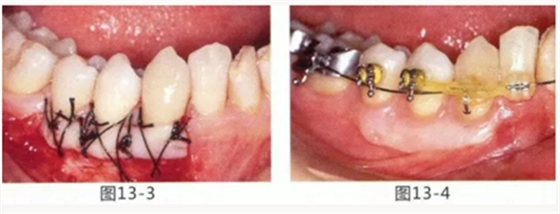

由于口腔前庭較淺且沒(méi)有附著齦,使菌斑容易滯留且刷牙困難的病例

圖13-1 使用碘溶液進(jìn)行染色,頰側(cè)基本看不到角化牙齦,且無(wú)口腔前庭的狀態(tài)。

圖13-2 為了擴(kuò)張口腔前庭,獲取附著齦而進(jìn)行了游離齦移植術(shù)。受皮床一定不能發(fā)生移動(dòng),盡可能使厚度均等。

圖13-3 手術(shù)剛結(jié)束的狀態(tài)。通過(guò)骨膜縫合的褥式縫合將移植片固定,使其無(wú)法移動(dòng)。

圖13-4 手術(shù)完成2年后的狀態(tài)??谇磺巴サ玫綌U(kuò)張,即使正在進(jìn)行正畸治療,也沒(méi)有妨礙到清潔。